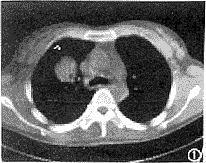

CT检查: 两肺野弥漫分布大小不等的类圆形高密度影,最大约为2.8cm×3.0cm大小,最小约0.3cm×0.4cm大小。病灶边缘清楚但不锐利。较大病灶中可见细支气管影,两肺纹理较重(图1、2)。CT诊断:两肺多发转移瘤。

图1、2 分别为纵隔窗和肺窗,两肺散在大小不等的类圆形高密度影,较大病灶内可见细支气管气相,两肺纹理较重